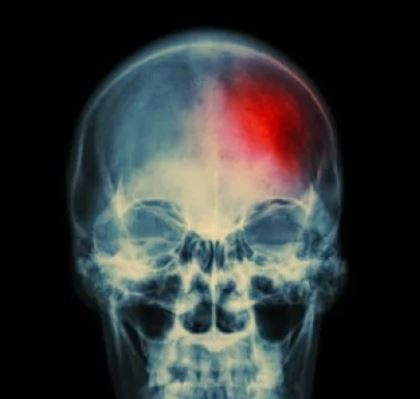

Преди инсулт тялото излъчва 7 тревожни сигнала

Всички имаме бегло понятие какво означава инсултът. Това е състояние, при което даден район на нашия мозък не получава нужното количество кислород и започва да умира. Грешката в измерване на кръвното налягане, която правят почти всички.

В тази статия ще ви разкажем за 7 признака, които показват предстоящо начало на инсулт. Ако забележите един или повече от няколко симптома, незабавно се консултирайте с лекар!